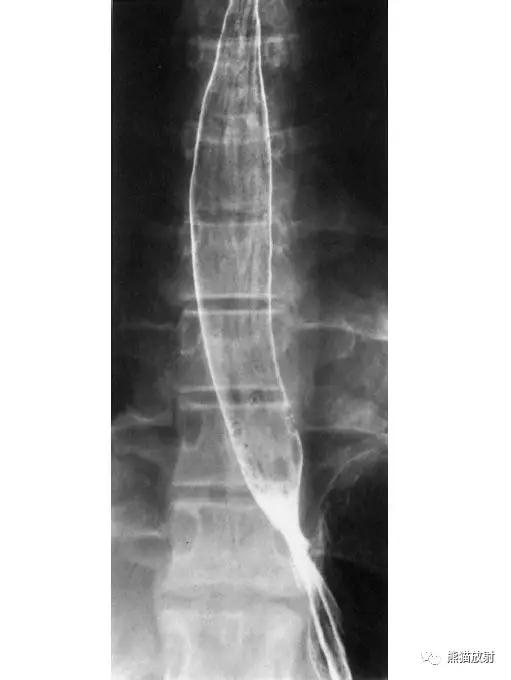

3 Esophagus 食管

1 Uvula 悬雍垂,2 Lateral glossoepiglottic fold 舌会厌外侧襞,3 Epiglottis 会厌,4 Piriform recess 梨状隐窝,5 Upper esophageal sphincter 食管上括约肌,6 Body of the esophagus 食管体部,7 Aortic arch 主动脉弓,8 Bronchial and aortic segment 支气管及主动脉段,A Paratracheal segment 气管旁段,B Aortic segment 主动脉段,C Bronchial segment 支气管段,D Interbronchial segment 支气管间段,E Retrocardiac segment 心后段,F Epiphrenic segment 膈上段